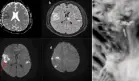

El análisis de orina mostró hematuria y proteinuria, mientras que los niveles de creatinina sérica eran normales. Una cistoscopia flexible ambulatoria no reveló hallazgos patológicos. Sin embargo, una urografía por tomografía computarizada (TC) evidenció ureterohidronefrosis derecha con una entrada estrecha a la vejiga, sin presencia de cálculos. También se observó la copa menstrual colocada en el lado derecho de la vagina, en proximidad directa al ostium ureteral derecho.

Ante estos hallazgos, se plantearon dos posibilidades: una obstrucción mecánica del uréter derecho causada por la copa menstrual o una estenosis ureteral posquirúrgica residual, resultado de la extracción previa del cálculo urinario en esa zona. Para evaluar la posible implicación de la copa menstrual, se indicó suspender su uso y se programaron estudios de seguimiento un mes después.

Tras retirar la copa, una ecografía mostró regresión completa de la ureterohidronefrosis. La renografía confirmó una función renal normal en ambos riñones, con distribución funcional equilibrada. La paciente no volvió a experimentar dolor ni hematuria, lo que respaldó el diagnóstico de obstrucción ureteral por compresión mecánica causada por la copa menstrual.